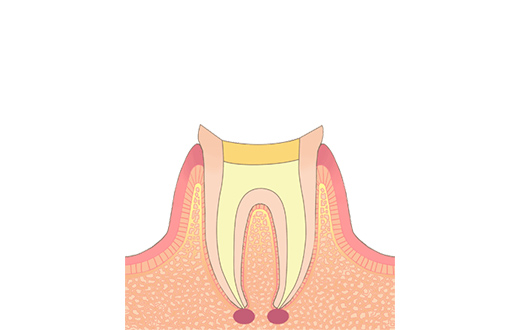

STEP05コア形成・印象

神経が入っていた部分は全て取り除かれ、お口の中に見えている頭の部分は空洞になっているので、その空洞を埋める土台の型取りを行います。

場合によっては、直接その空洞を埋める処置を行うこともあります。型取りをした場合は、後日土台を装着し、被せ物の型を採ります。 -